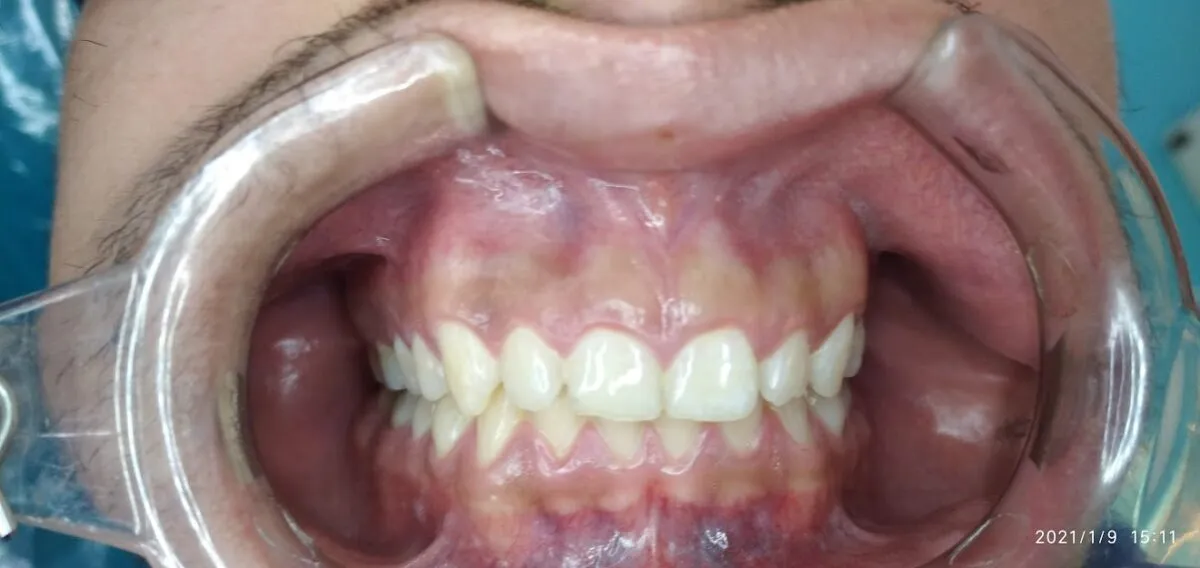

In this article we will show you a case of gingivectomy from before, during and after